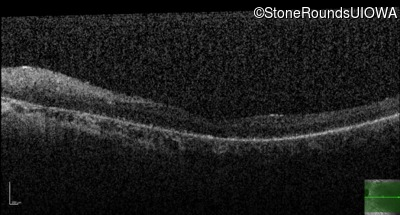

Optical Coherence Tomography - Right - 5/225

Exemplar / OCT Stack